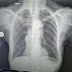

Casos Clínicos: Mujer de 74 años con tabaquismo severo y síntomas respiratorios

Buena tardes doctor. Le muestro unas radigrafias de una paciente de 74 años blanca bajo peso para su talla fumadora inveterada hipertensa ...